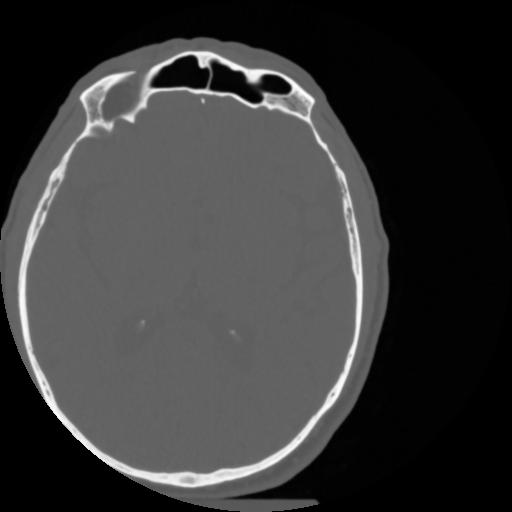

4 CEREBRO,,Vol,0.5,CEREBRO,,